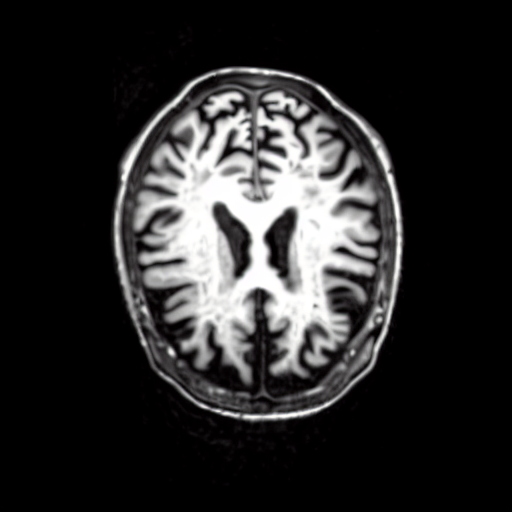

We present the results of conditional medical image generation with and without our proposed method LD, in Tab. 1, and Fig. 5. In Fig. 4, we show examples of brain MR images generated by the different methods combined with LD for two different classes of cognitively normal (CN) and Alzheimer’s disease (AD). The results were obtained by fine-tuning the corresponding method on the medical data with LD. As shown in Fig. 4, the samples generated through Custom Diffusion tuning are realistically looking while understanding the difference between CN and AD brain properly, which other methods failed at. Textual inversion seems to understand the concept but fails to understand the brain structure properly. Quantitative results on the performance of all our methods are presented in Tab. 1. Qualitative results on the CheXpert [19] dataset, along with a user study and ablation of different parameters, optimization algorithm, and more, are included in the supplementary material.

Qualitatively, Fig. 5 shows a significant improvement of the visual realism across all methods when using a drift of . The background is consistently black as in real brain MR images; the shape of the brain becomes more realistic, and the white and gray matter structure improves. For an analytical evaluation, we calculated the FID between our test data and 200 synthetically generated images from each method (100 CN, 100 AD). The results in Tab. 1 demonstrate that LD improves the ability of the model to generate realistic MRI slices for both healthy brains and brains with Alzheimer’s disease. For this reason, all following experiments were done with LD.